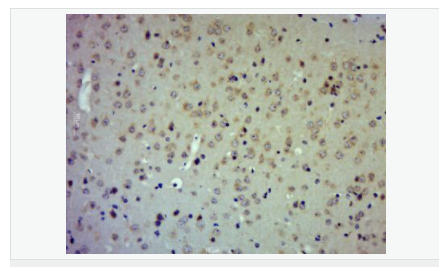

| 產品應用 | WB=1:500-2000 IHC-P=1:100-500 IHC-F=1:100-500 ICC=1:100-500 IF=1:100-500 (石蠟切片需做抗原修復) not yet tested in other applications. optimal dilutions/concentrations should be determined by the end user. |